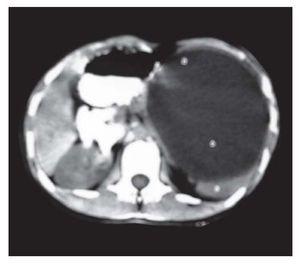

Mujer de 14 años de edad sin antecedentes heredofamiliares ni patológicos relevantes, que a los 11 años de edad sufrió una caída de 50 cm de altura, con golpe directo en la región dorsolumbar izquierda, al parecer asintomática. Un mes antes de acudir a la consulta, refirió que tras un traumatismo leve (caída de su propia altura), su madre observó un aumento de volumen en el hemiabdomen superior izquierdo y la trajo a consulta; se informa que la paciente había tenido episodios recurrentes de dolor abdominal leve. A la exploración física, se observó el hipocondrio izquierdo aumentado de volumen y se palpó una esplenomegalia hasta 8 cm por debajo del reborde costal, con escaso dolor a la palpación profunda. El ultrasonido abdominal reveló la presencia de una lesión quística al parecer dependiente del bazo. La tomografía computarizada de abdomen evidenció una lesión de aspecto quístico de 12 x 10 x 8 cm en el polo superior esplénico (Figura 1). Ante la sospecha de un hematoma por el traumatismo reciente, se realizó una laparotomía exploradora. Se accedió a la cavidad abdominal a través de una incisión media supraumbilical y se encontró el bazo aumentado de tamaño, con adherencias laxas parietales, al diafragma, estómago y duodeno. Se efectuó la esplenectomía, cuya hemostasia se obtuvo mediante colocación de esponja, y se dejó un drenaje tipo Penrose. La evolución posoperatoria fue satisfactoria.

Figura 1. Tomografía computarizada del abdomen con contraste oral que demuestra la lesión quística esplénica.